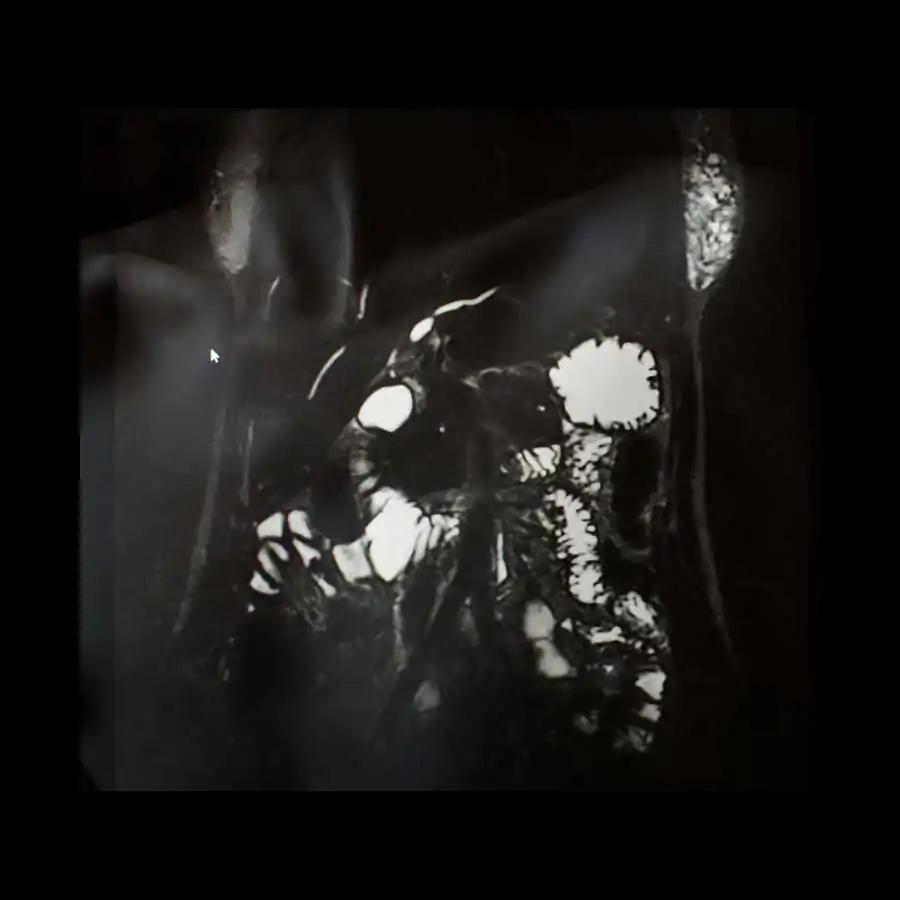

The project ‘Limits of existence’ are self-portraits compiled by the author with MRI scans. It is a case-record, in which the body appears as a subject to internal researches and the only way of communication with the outside world.

Working with the fear of physical existence termination, the author examines the physiological processes that occur during her illness with the threat of death, as the only real manifestation of life, as the limits of the possible. All thoughts, feelings and experiences, focused on physical sensations, force the author to reconsider the meaning of ‘Me’, ‘person’, ‘soul’; also the question of possibility for the spirit to overcome the boundaries of the body or expand them is raised. [Official Website]